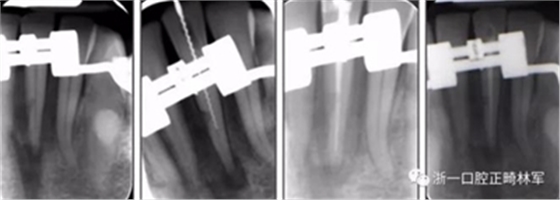

術(shù)后第9天開始旋轉(zhuǎn)擴弓器,每天轉(zhuǎn)2次,每次轉(zhuǎn)90度,即擴開0.5mm。每隔1周進行檢查,目標上頜擴開9mm,下頜擴開6mm。18天后,上頜中切牙間出現(xiàn)8mm間隙。下頜出現(xiàn)6mm間隙,(于13天出現(xiàn)后,停止旋轉(zhuǎn)擴弓器)。在擴弓器旋轉(zhuǎn)3天后,拍片發(fā)現(xiàn)左下頜中切牙遠中牙根中段有一條低密度陰影,臨床冷熱診反應(yīng)遲鈍,可能為術(shù)中損傷所致。牙體牙髓科會診,建議行根管治療,故行根管治療。

擴弓保持8周后,除擴弓器影響牙外粘接托槽,使用0.014鎳鈦絲進行排齊、整平。旋轉(zhuǎn)停止后3個月拆除擴弓器,全口粘接托槽,使用0.016niti繼續(xù)排齊整平。佩戴可摘保持器,保持上頜寬度。在使用至0.018x0.018niti7周,徹底排齊整平后,使用大弓型的0.016x0.022不銹鋼絲,繼續(xù)維持原有寬度,同時停止使用可摘保持器。掛II類牽,糾正磨牙關(guān)系,使用鏈圈關(guān)閉散在間隙,少量使用IPR去除局部前牙的黑三角。術(shù)后9個月拍全景示,牙根平行度可,再無其他牙根出現(xiàn)問題。1年7個月后治療結(jié)束。上下頜3-3舌側(cè)保持器+哈雷氏保持器進行保持。